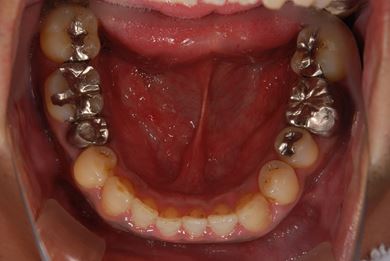

治療前

• 治療前